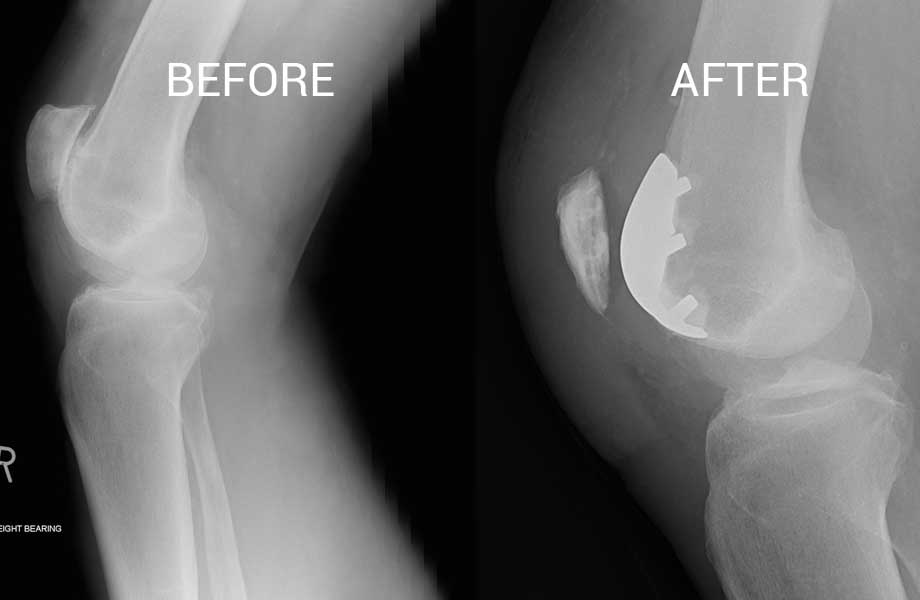

Knee cap replacement xrays. Titanium implant. Osteoarthritis. Articular Knee Cap Replacement It is an alternative to total knee replacement for people with osteoarthritis that affects only the patellofemoral compartment. a surgical option for osteoarthritis affecting the back of the kneecap, involving a metal and plastic prosthesis. It is caused by cartilage damage in the. knee cap replacement, also known as patellofemoral replacement, is a specialized orthopaedic surgery aimed at. Knee Cap Replacement.